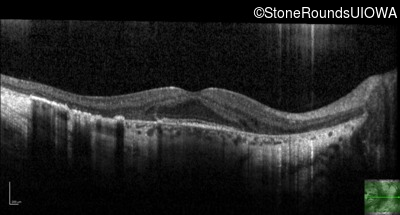

Age at visit: 37 years

This 35-year-old man has trouble in low light and when moving around in busy places. He first reported trouble seeing in low light at age 13. His maternal grandfather was similarly affected.